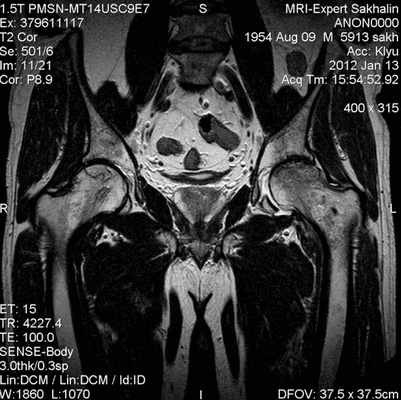

(Справа) МРТ Т1ВИ, коронарный срез: определяется латеральный вывих бедренно-большеберцового сустава. Крестовидная и медиальная коллатеральная связки разорваны. Подвздошно-большеберцовый пучок не поврежден.

(Справа) Рентгенография в аксиальной проекции: у этого же пациента определяется латеральный вывих большеберцовой кости и надколенника по отношению к бедренной кости. Признаки перелома отсутствуют. (Слева) МРТ после вывиха коленного сустава, РDВИ, режим подавления сигнала от жира, аксиальный срез: вклинивание подколенного сухожилия в латеральное ложе колена. Это обстоятельство полсужило препятствием для адекватной репозиции вывиха. Отмечается латеральный мениск рядом с сухожилием.

(Справа) МРТ Т2ВИ, режим подавления сигнала от жира, коронарный срез: у этою же пациента определяется отрыв объединенною сухожилия в месте ею прикрепления к головке малоберцовой кости. ЗКС разорвана. Подколенное сухожилие входит в заднее ложе сустава и вклинено там. (Слева) МРТ Т2ВИ, режим подавления сигнала от жира, коронарный срез: на более фронтальном срезе у этою же пациента визуализируется подколенное сухожилие, вклиненое между большеберцовой костью и латеральным мениском. Это было подтверждено на операции.

(Справа) MPT PDBИ, сагиттальный срез: определяется отрыв ПКС в месте ее прикрепления к большеберцовой кости. Подколенное сухожилие находится между большеберцовой костью и латеральным мениском.